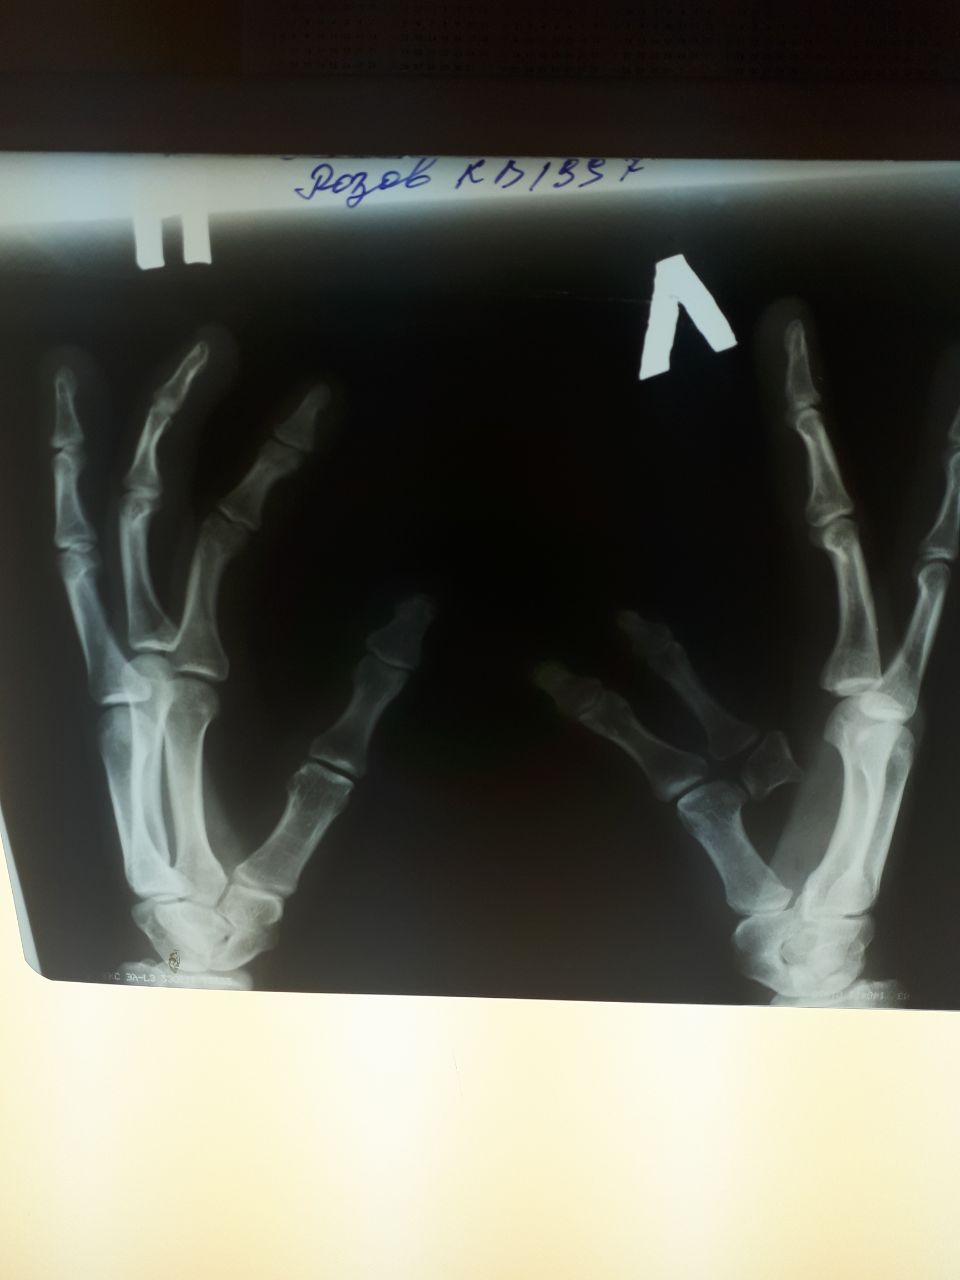

Помогите пожалуйста с описанием

Правая кисть представлена 4я лучами, и перечисление костей запястья.

Левая кисть 3я лучами, первый из которых представлен удвоенным пальцем, в виде гипопластичных двух фаланг и головкой пястной кости.

ВАР кистей: четырехпалая правая кисть, трехпалая левая кисть с неполным удвоением первого луча (без диафиза и основания).